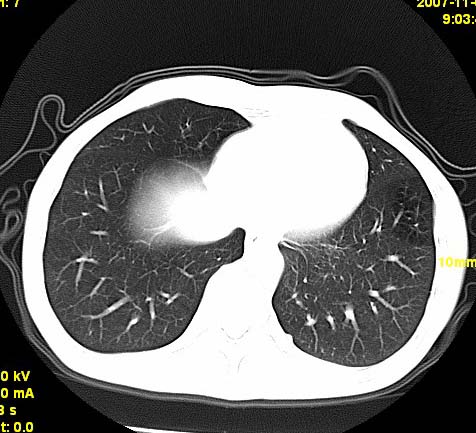

以下是引用wangzhengyuan在2007-11-11 23:31:00的发言:[br]钙化灶,看上去不像转移。

以下是引用zjzjr在2007-11-12 8:35:00的发言:[br]考虑错构瘤,建议定期复查.

以下是引用卜一在2007-11-12 5:59:00的发言:[br]病灶本身不像转移,不知有没有以前的胸部ct片,若有,则可以对比以下,若是新出现病灶,应高度警惕“转移”的可能![br]